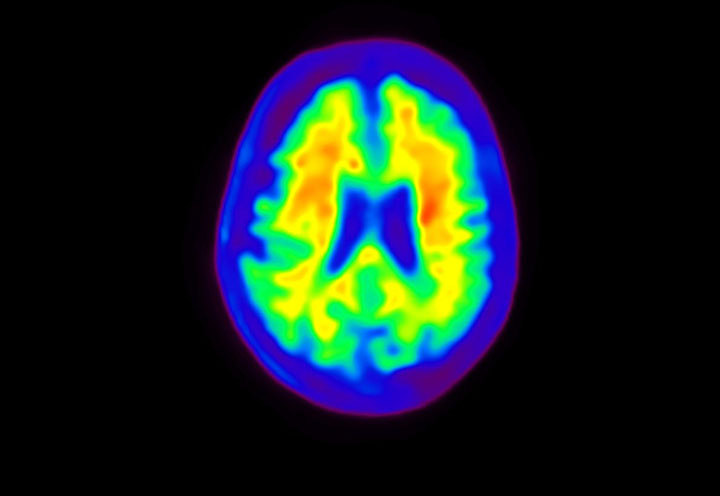

Head / Case4 : Amyloid

Courtesy : Kindai University Hospital

- Imaging protocol

- Injected dose: 3.21 MBq/kg, 18F-Flutemetamol

- Uptake time: 100 minutes

- Scan time: 20 minutes